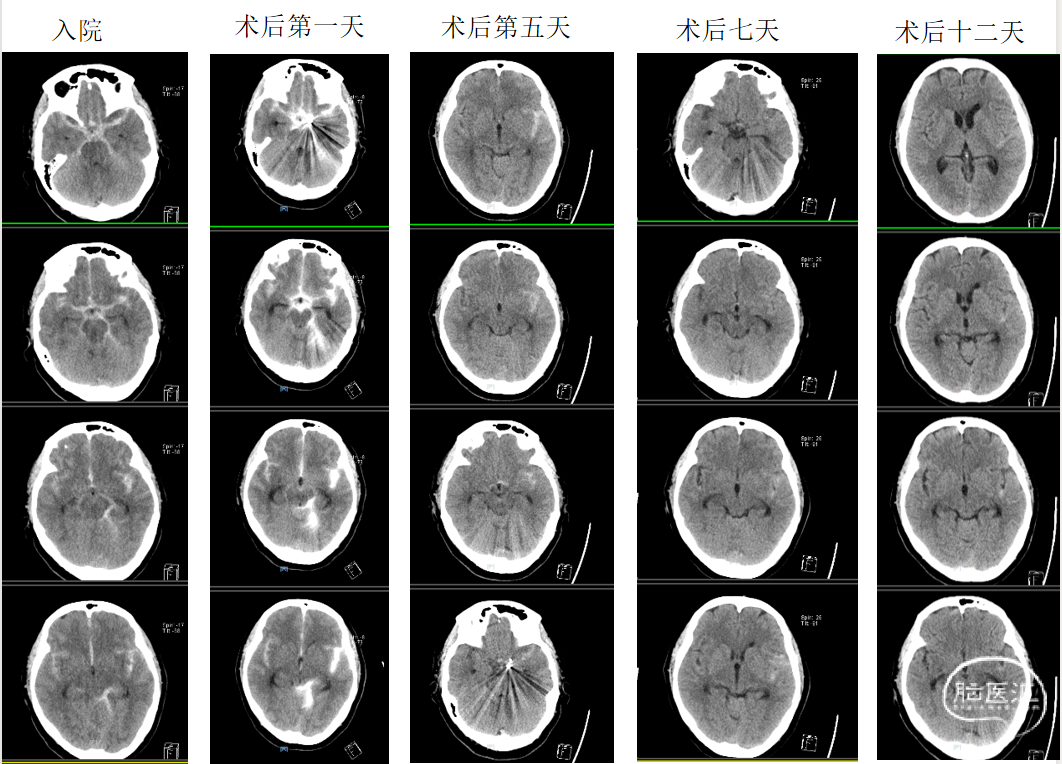

术后第一天,患者神志清楚,失语,精神差,查体配合。左上肢肌力2级,左下肢肌力1级,右上肢肌力5级,右下肢肌力4级。

患者BNP高,术后第二天,给予硝酸异山梨酯注射液减轻心脏负荷。术后第二天夜间语言基本恢复。

术后第三天查核磁:动脉瘤术后改变,蛛网膜下腔、脑室积血。双侧颞顶叶散多发脑梗塞。考虑左侧肢体活动不利为右侧脑梗塞所致。

2022-7-12复查(术后第7天):头颅血管术后改变,蛛网膜下腔出血、脑室积血有吸收。病人头痛明显,腰穿压力330,给予甘露醇250ml Q12h

2022-7-5入院,昏迷,GCS6分。

2022-7-6术后第一天,神清,失语,左侧偏瘫,急性非ST段抬高型心肌梗死 。腰穿!

2022-7-7术后第二天,夜间语言基本恢复,左上II级,左下I级。腰穿!

2022-7-8术后第三天,语言正常,MRI右侧脑梗塞,考虑血管痉挛所致。腰穿!

2022-7-10术后第五天,左手指活动正常,握力稍弱,上臂可抬离床面。腰穿!

2022-7-12术后第七天,左手指活动正常,上肢可抬离床面并抵抗,自觉发沉。腰穿!

腰穿压力高,给予加用甘露醇。

2022-7-14复查头颅CT+CTA:蛛网膜下腔积血明显减少。

2022-7-17停甘露醇,坐位活动。左侧肢体肌力4级。